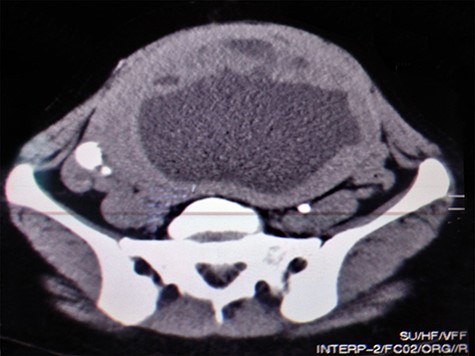

A 51-year-old woman (G 17, P 15, Ab 2) presented to the emergency department with low abdominal pain. Her gynecological history reveals pelvic pressure, irregular menstruation and menorrhagia during the past 3 months. She stated that all her pregnancies were delivered vaginally. Otherwise, neither her medical, surgical nor familial history was significant. At admission, her vital signs were in the normal range, she had mild pallor, she was afebrile and did not complain of nausea or vomiting. Her physical examination showed abdominal distention, enlarged uterine, equals to 20 weeks’ gestation. The remaining of her systemic examination was unremarkable. The patient’s laboratory tests showed microcytic anemia [RBCs: 4.42 × 106/ul, Hb: 11.2 g/dl, Hematocrit: 31.5%, MCV: 71.2 fl] and a slight increase in platelets count [403 × 103/ul] with normal white blood cell count. Her liver and kidney function were sufficient. Normal CA-125 and alpha-fetoprotein levels excluded any concerns about sarcomatous changes in leiomyoma; we were unable to perform the MRI and isoenzyme testing because they are high-priced investigations. Beta-hCG levels were normal, which exclude ectopic pregnancy. Doppler ultrasound was unavailable in our department; hence, we used normal ultrasound to rule torsion or rupture of any ovarian cysts. Both transvaginal and transabdominal ultrasound showed a large heterogeneous mass in uterine wall (Fig. 1). Pelvic CT scan reported an irregular mass measures 20 × 17 cm with central necrosis (Fig. 2).